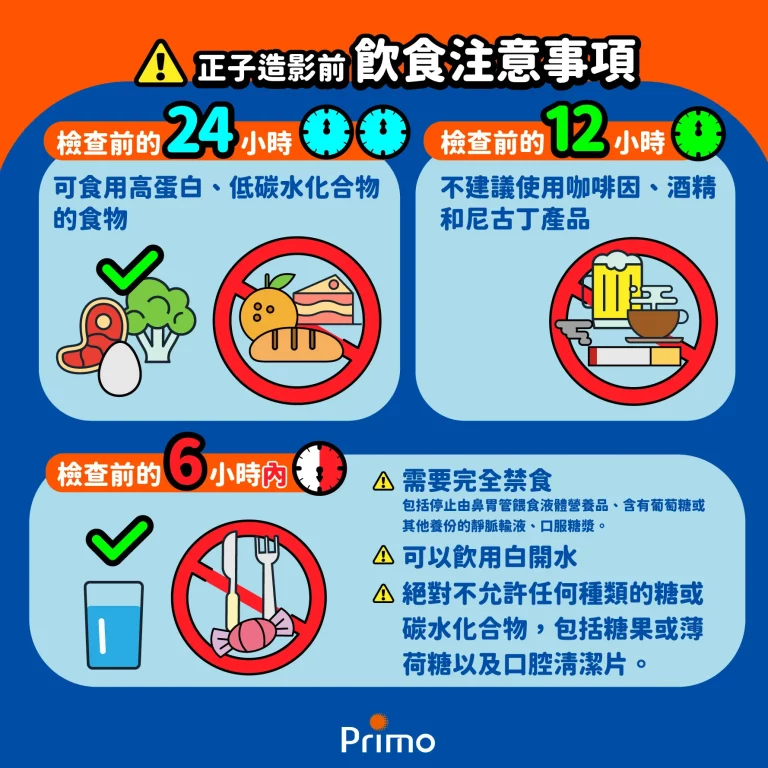

放射性氟化去氧葡萄糖(F-18 FDG)正子斷層造影前的準備事項